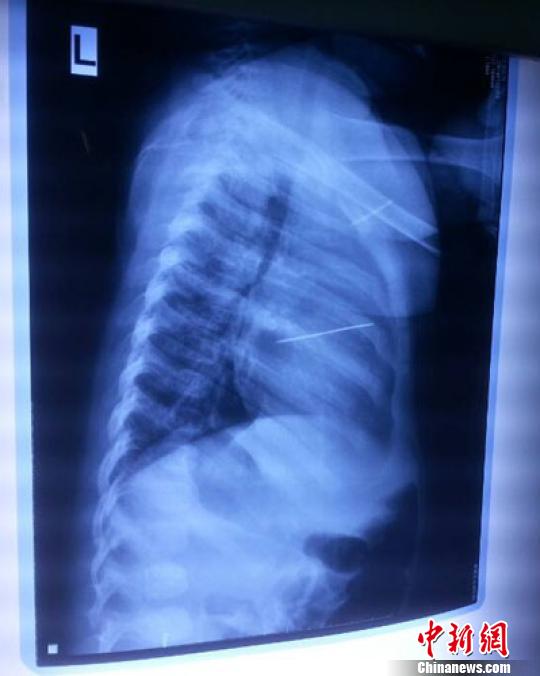

女嬰胸片提示心臟里面扎了一個縫衣針 蔡迅翔 攝

醫(yī)院胸心外科主任翟波介紹說,1月22日,小患者彤彤因為發(fā)燒抽搐來醫(yī)院就診,常規(guī)檢查時發(fā)現(xiàn)孩子心臟里面扎了一個縫衣針。

“第二天上午,我們做了個緊急彩超檢查,發(fā)現(xiàn)針是從患者右心室表面刺入,穿破室間隔,到達左心房,中間還有一部分損害到二尖瓣。于23號下午,我們就做了一個緊急手術,手術中發(fā)現(xiàn),這枚針已經(jīng)刺入心臟,沒入了右心室的下面,表面已經(jīng)看不到針了,僅能看到一個小針眼,還在往外滲血,一點一點的滲,心包腔里面大概有100多毫升的出血,心包上一個洞,針在右心室表面刺入以后,穿過室間隔,在二尖瓣的上方,進入了左心房,在針的四周,有很多纖維沉積物,包繞著這枚針。”翟波說,他們把針取出來以后,測量了一下,長度大概是五厘米,同時發(fā)現(xiàn)這個針給患者左心房的后壁造成了一定的損傷,左心房的后壁已經(jīng)損傷了三分之二,還剩下有左心房的外膜,很薄的一層,如果這一層再破的話,這個孩子將會引起大出血,很快就會死亡。